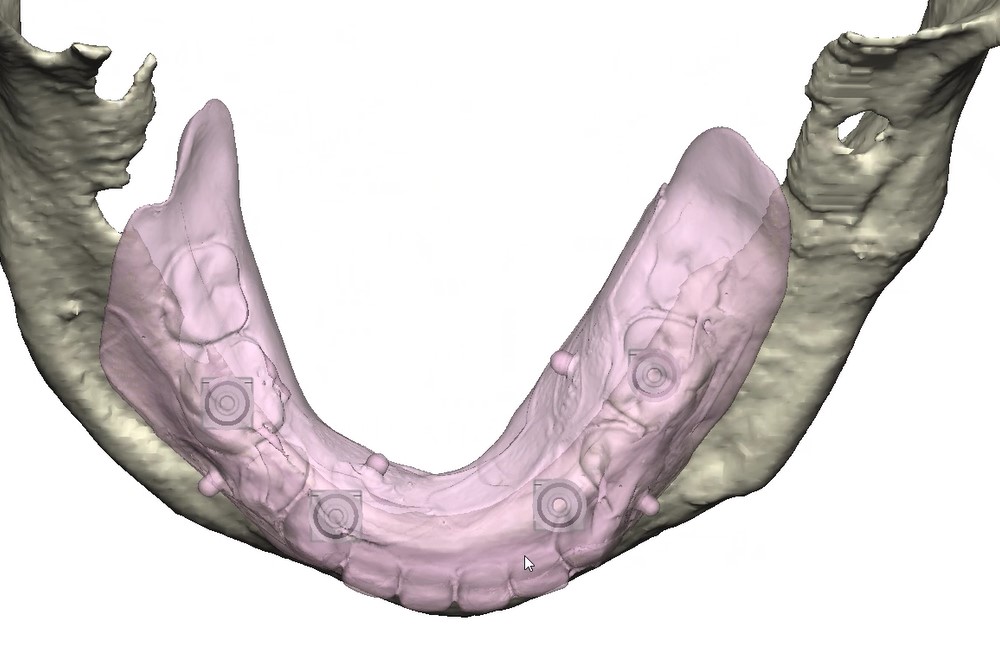

Records for this patient were collected using a dual-scan CBCT and intraoral scanning. A surgical planning session was completed with KLS Martin for the fabrication of a CAD-CAM subperiosteal implant system with immediate loading of a mandibular prototype (Figs 2-5).

A 3D-printed mandibular model with the subperiosteal system and prototype in place was also fabricated (Figs 6 and 7).

• Stereophotography scans of the cast were performed with the prototype in place and after removal with ICam4D scan bodies using Trios 4 Wireless Pod (3Shape) (Figs 12-14).